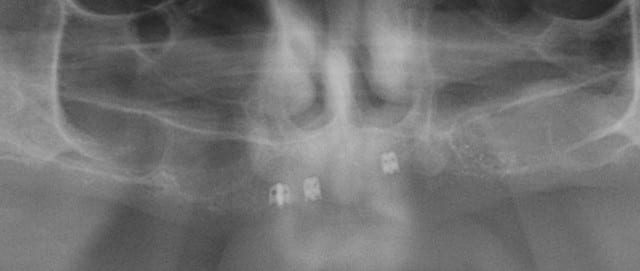

deux implants posés en 1994 et les deux vis de faux moignon sont cassees dans les deux implants

il s'agit de fx moignons monoblocs cad non transvissés

ceux que l'on vissait sur les implants tbr impactés

pas pour te faire peur, mais pratiquement indévissable (matage à froid) expérience perso...

les implants sont vraiment solide?

ils peuvent ne tenir que par la "croix" apicale comme là

sinon en pratique cela donne çà